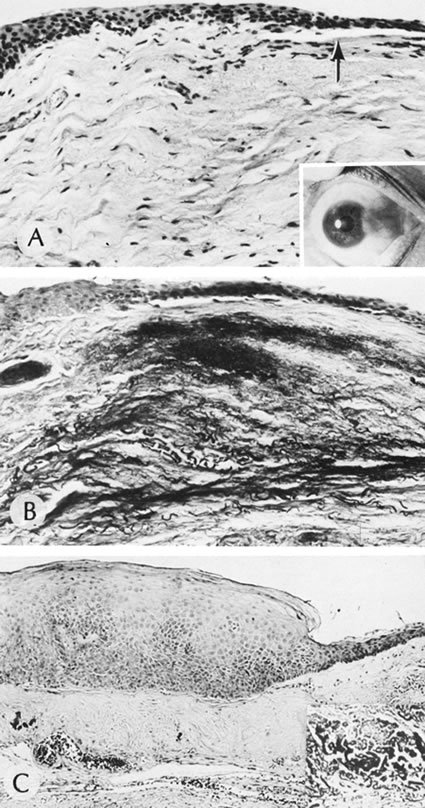

There are multiple nonspecific types of congenital corneal opacities. Although arrested embryogenesis or intrauterine inflammation may cause the entity, the opacities have the same clinical characteristics as acquired changes following trauma. In order of progressive severity, the degree of opacification is called a facet when only Bowman's membrane is involved; a nebula when the area of opacification is diffuse, cloudlike, and has indistinct borders; a macula when the area is dense and has a circumscribed border; and a leukoma when the cornea is opaque. Adherent leukoma is a subgroup in which a portion of iris is fused to the posterior surface of the opaque corneal tissue, similar to the findings of some healed acquired corneal perforations (Fig. 2).

Fig. 2. Adherent leukoma. A. Proliferated fibrous tissue attaches the iris to the cornea through a gap in Descemet's membrane of a 3-week-old wound. An overlying scar(s) is present through the full thickness of the cornea. After organization and shrinkage of the fibrous membrane, the scar will look much like the scar of adherent leukoma seen in B. Peripheral adherent leukoma (arrow) in a 12-year-old girl who had accidental perforation of the globe by a pair of scissors 5 weeks previously. The perforation of the cornea was repaired on the day of the injury. Sympathetic uveitis developed 2 days before the photograph was taken. C. The peripheral iris is adherent to the corneal stroma through a gap in Descemet's membrane. The overlying stroma is scarred. (Courtesy of SEI Photoarchives.)